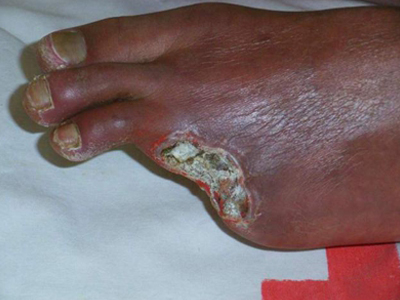

血栓闭塞性脉管炎又称Buerger病,是一种以中、小动脉节段性,非化脓性炎症和动脉腔内血栓形成为特征的慢性动脉闭塞性疾病。主要侵袭四肢,尤其是下肢的中、小动脉和静脉,引起患肢远侧段缺血性病变,出现肢体疼痛、皮肤颜色改变以及坏疽等症状。

肢体缺血可引起程度不同的皮肤干燥、脱屑、患肢肌肉萎缩、肢体变细等。肢端动脉搏动减弱或消失,肢体缺血的最严重后果为肢端坏疽或溃疡。